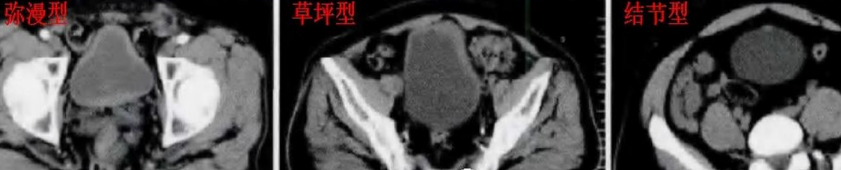

好发部位位于膀胱三角区及膀胱颈部,CT 表现为膀胱壁增厚、隆起性病变,多>5 mm,宽基底,病灶边缘光滑,隆起内可见囊变或钙化。增强后轻度强化,较邻近正常膀胱壁密度相似,膀胱外壁光整,局部输尿管壁可受累,一般无盆腔淋巴结肿大。影像学分型:草坪型-膀胱壁内节段性增厚;弥漫型-膀胱壁弥漫性增厚;结节型-膀胱内壁结节样隆起,表面光整、宽基底(钝角)。本病例 1 属于弥漫型,病例 2 属于草坪型。